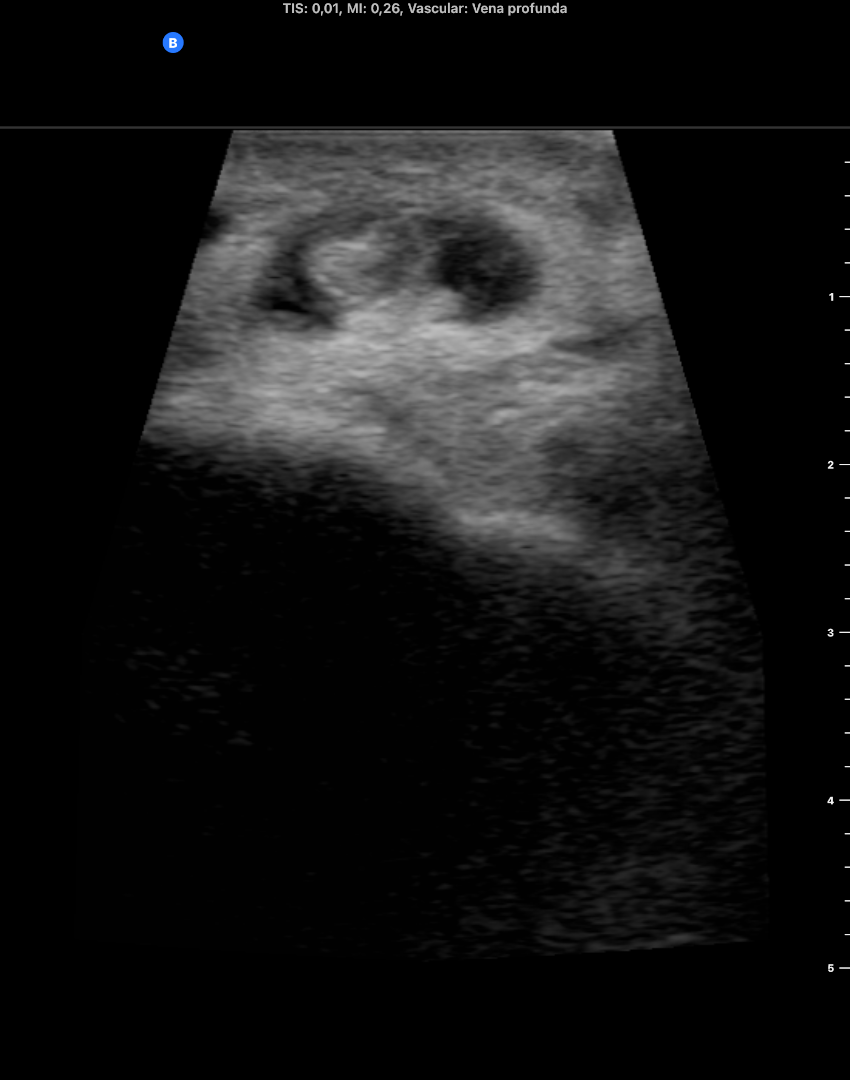

Descripción de los hallazgos ecográficos y las imágenes más relevantes para la resolución del caso

EcoscopiAP: líquido peritendinoso alrededor del tendón del m tibial anterior. Mínimo edema del tj cel sc. No TVP.